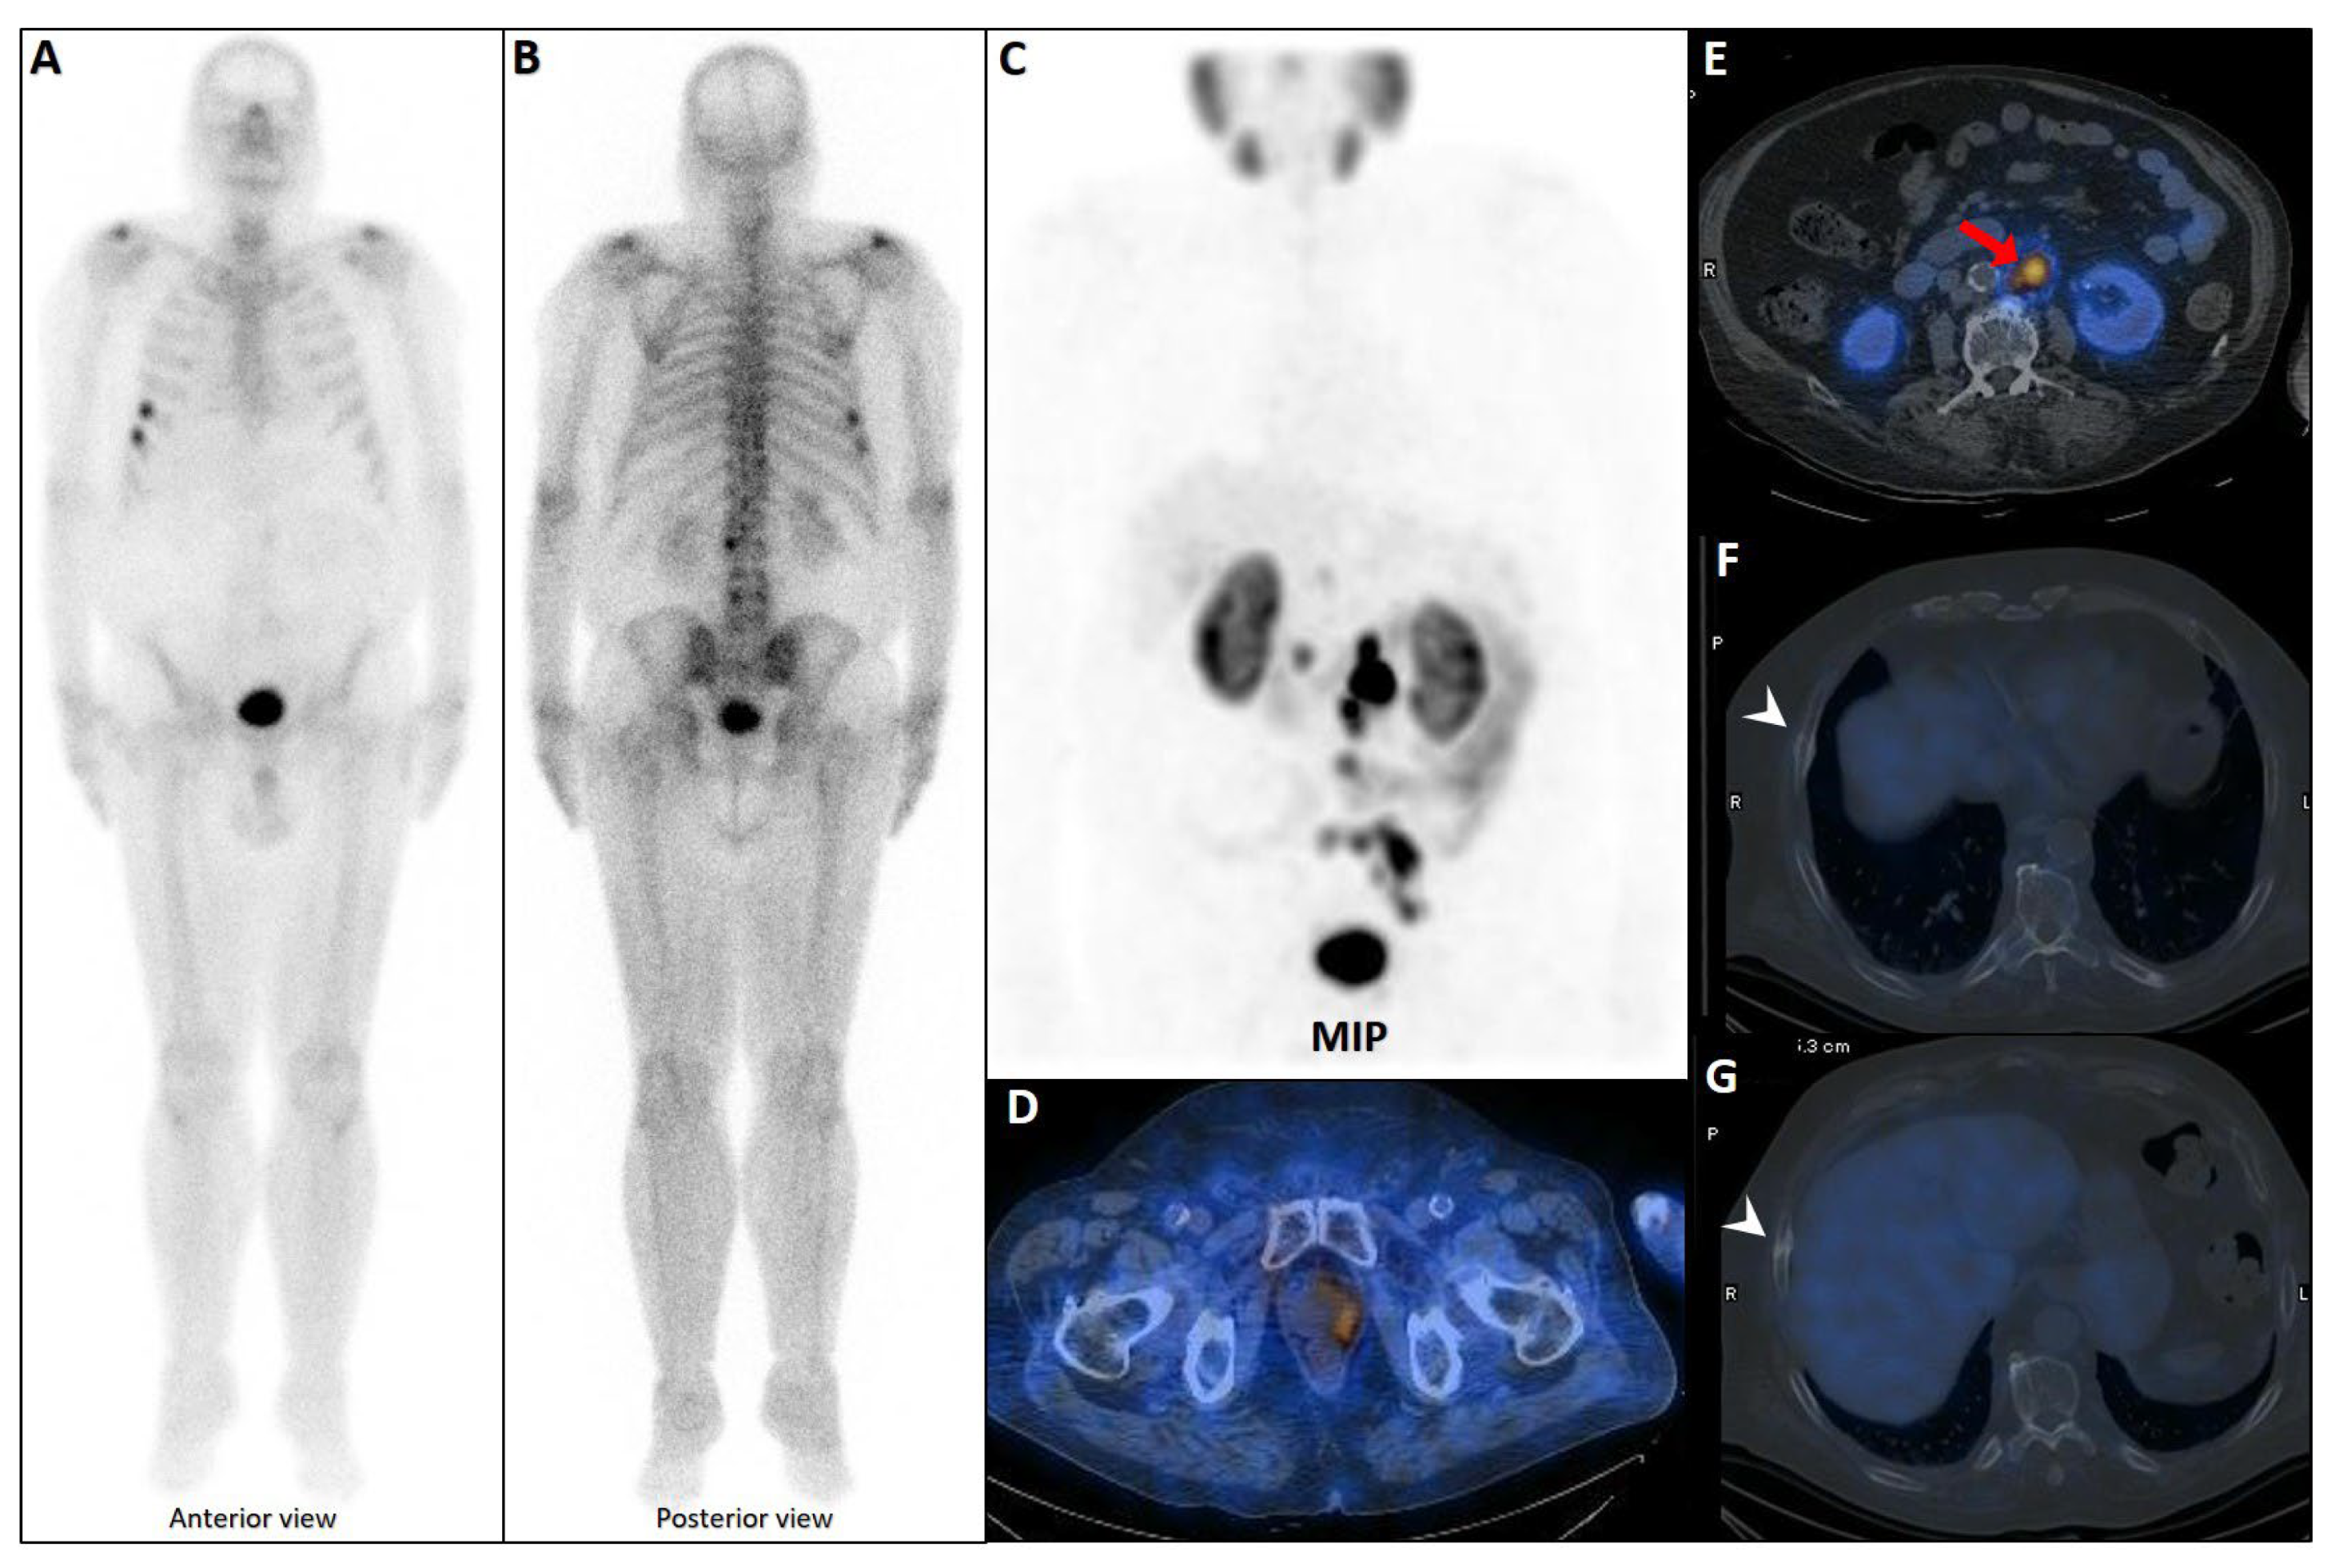

Figure 3.

False positive findings in bone scintigraphy due to rib fractures. A 78-year-old man with prostate adenocarcinoma (biopsy Gleason score 4 + 4, serum PSA = 56.8 ng/mL) was referred for staging. Whole-body bone scan revealed two consecutive focal osteoblastic activities in the lateral arc of the ribs on the right side (A,B). 99mTc-PSMA SPECT/CT (C) revealed increased tracer uptake in the prostate gland (D), multiple metastatic lymphadenopahies on the left side of pelvis and para-aortic regions (red arrow, (E)). Moreover, fractures in the right 6th and 7th ribs showed no PSMA avidity (white arrowheads, (F,G)).

5.2. Bone Scintigraphy: High Sensitivity but Lack of Specificity

Bone scintigraphy, typically using 99mTc-methylene diphosphonate (MDP), is becoming an outdated or even obsolete method for detecting skeletal metastases, including rib involvement [100,116,117]. Historically, its strengths included high sensitivity, as it could identify osteoblastic activity before structural alterations become evident, and the ability to screen the entire skeleton in a single session. However, its specificity was limited, and it frequently yielded false positives, as degenerative changes, healing fractures (Figure 3), or infections can mimic metastatic lesions [118]. Furthermore, it cannot reliably differentiate PCa metastases from other malignant or benign bone conditions [119].